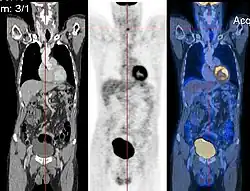

CT image (left), PET image (center) and overlay of both (right) after correct registration

Image registration is a process that searches for the correct alignment of images.[21][22][23][24] In the simplest case, two images are aligned. Typically, one image is treated as the target image and the other is treated as a source image; the source image is transformed to match the target image. The optimization procedure updates the transformation of the source image based on a similarity value that evaluates the current quality of the alignment. This iterative procedure is repeated until a (local) optimum is found. An example is the registration of CT and PET images to combine structural and metabolic information (see figure).